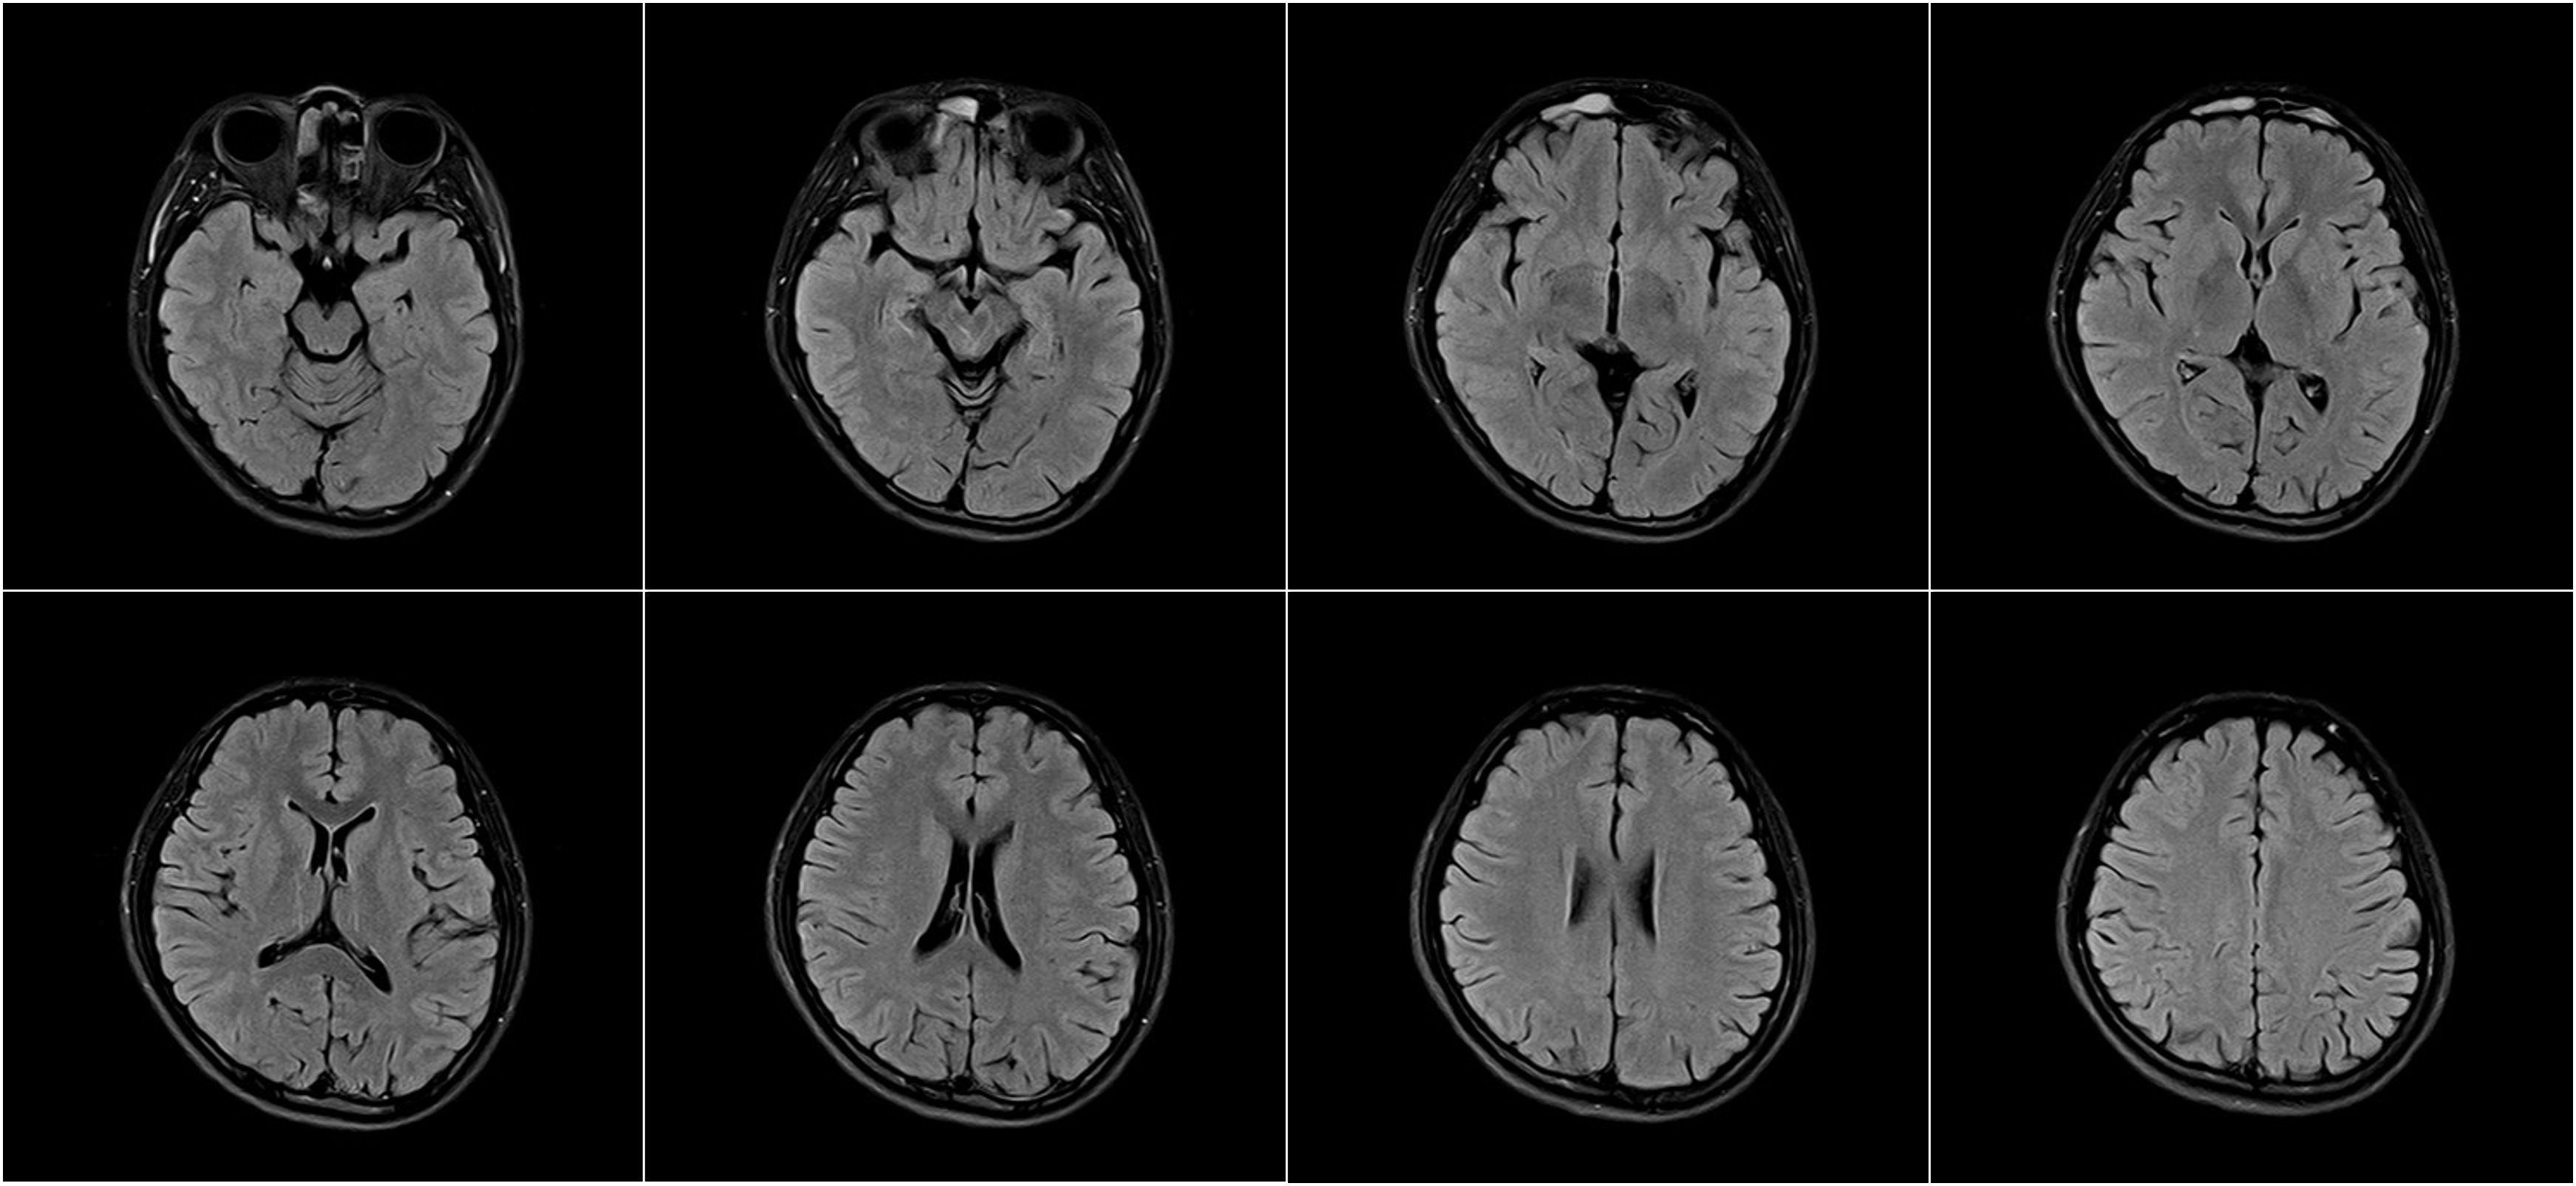

Hình ảnh lâm sàng